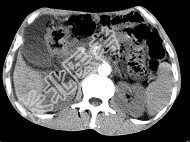

单项选择题女,50岁, 中上腹疼痛,消瘦乏力, 影像检查如下图,最佳的诊断为( )

A、胰岛素瘤

B、慢性胰腺炎

C、急性胰腺炎

D、腹膜后淋巴瘤

E、胰腺癌并腹膜后淋巴结转移